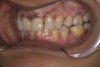

Fig 2. Preoperative frontal retracted 1:2 view.

Figure 2

A 40-year-old female patient complained of short teeth and asked for various options to improve her smile. On clinical examination, the palatal surfaces of the maxillary anterior teeth were found to be eroded, with the residual tooth structure having a smooth and shiny appearance (Figure 1 through Figure 3). In MIP, no restorative space was available, as the lower anterior teeth fit tightly into the upper palatal surfaces, making this a clinically challenging situation to treat conservatively. In most cases of conventional treatment protocols, such upper teeth are devitalized and restored with crowns that structurally leave the teeth in a compromised condition.10